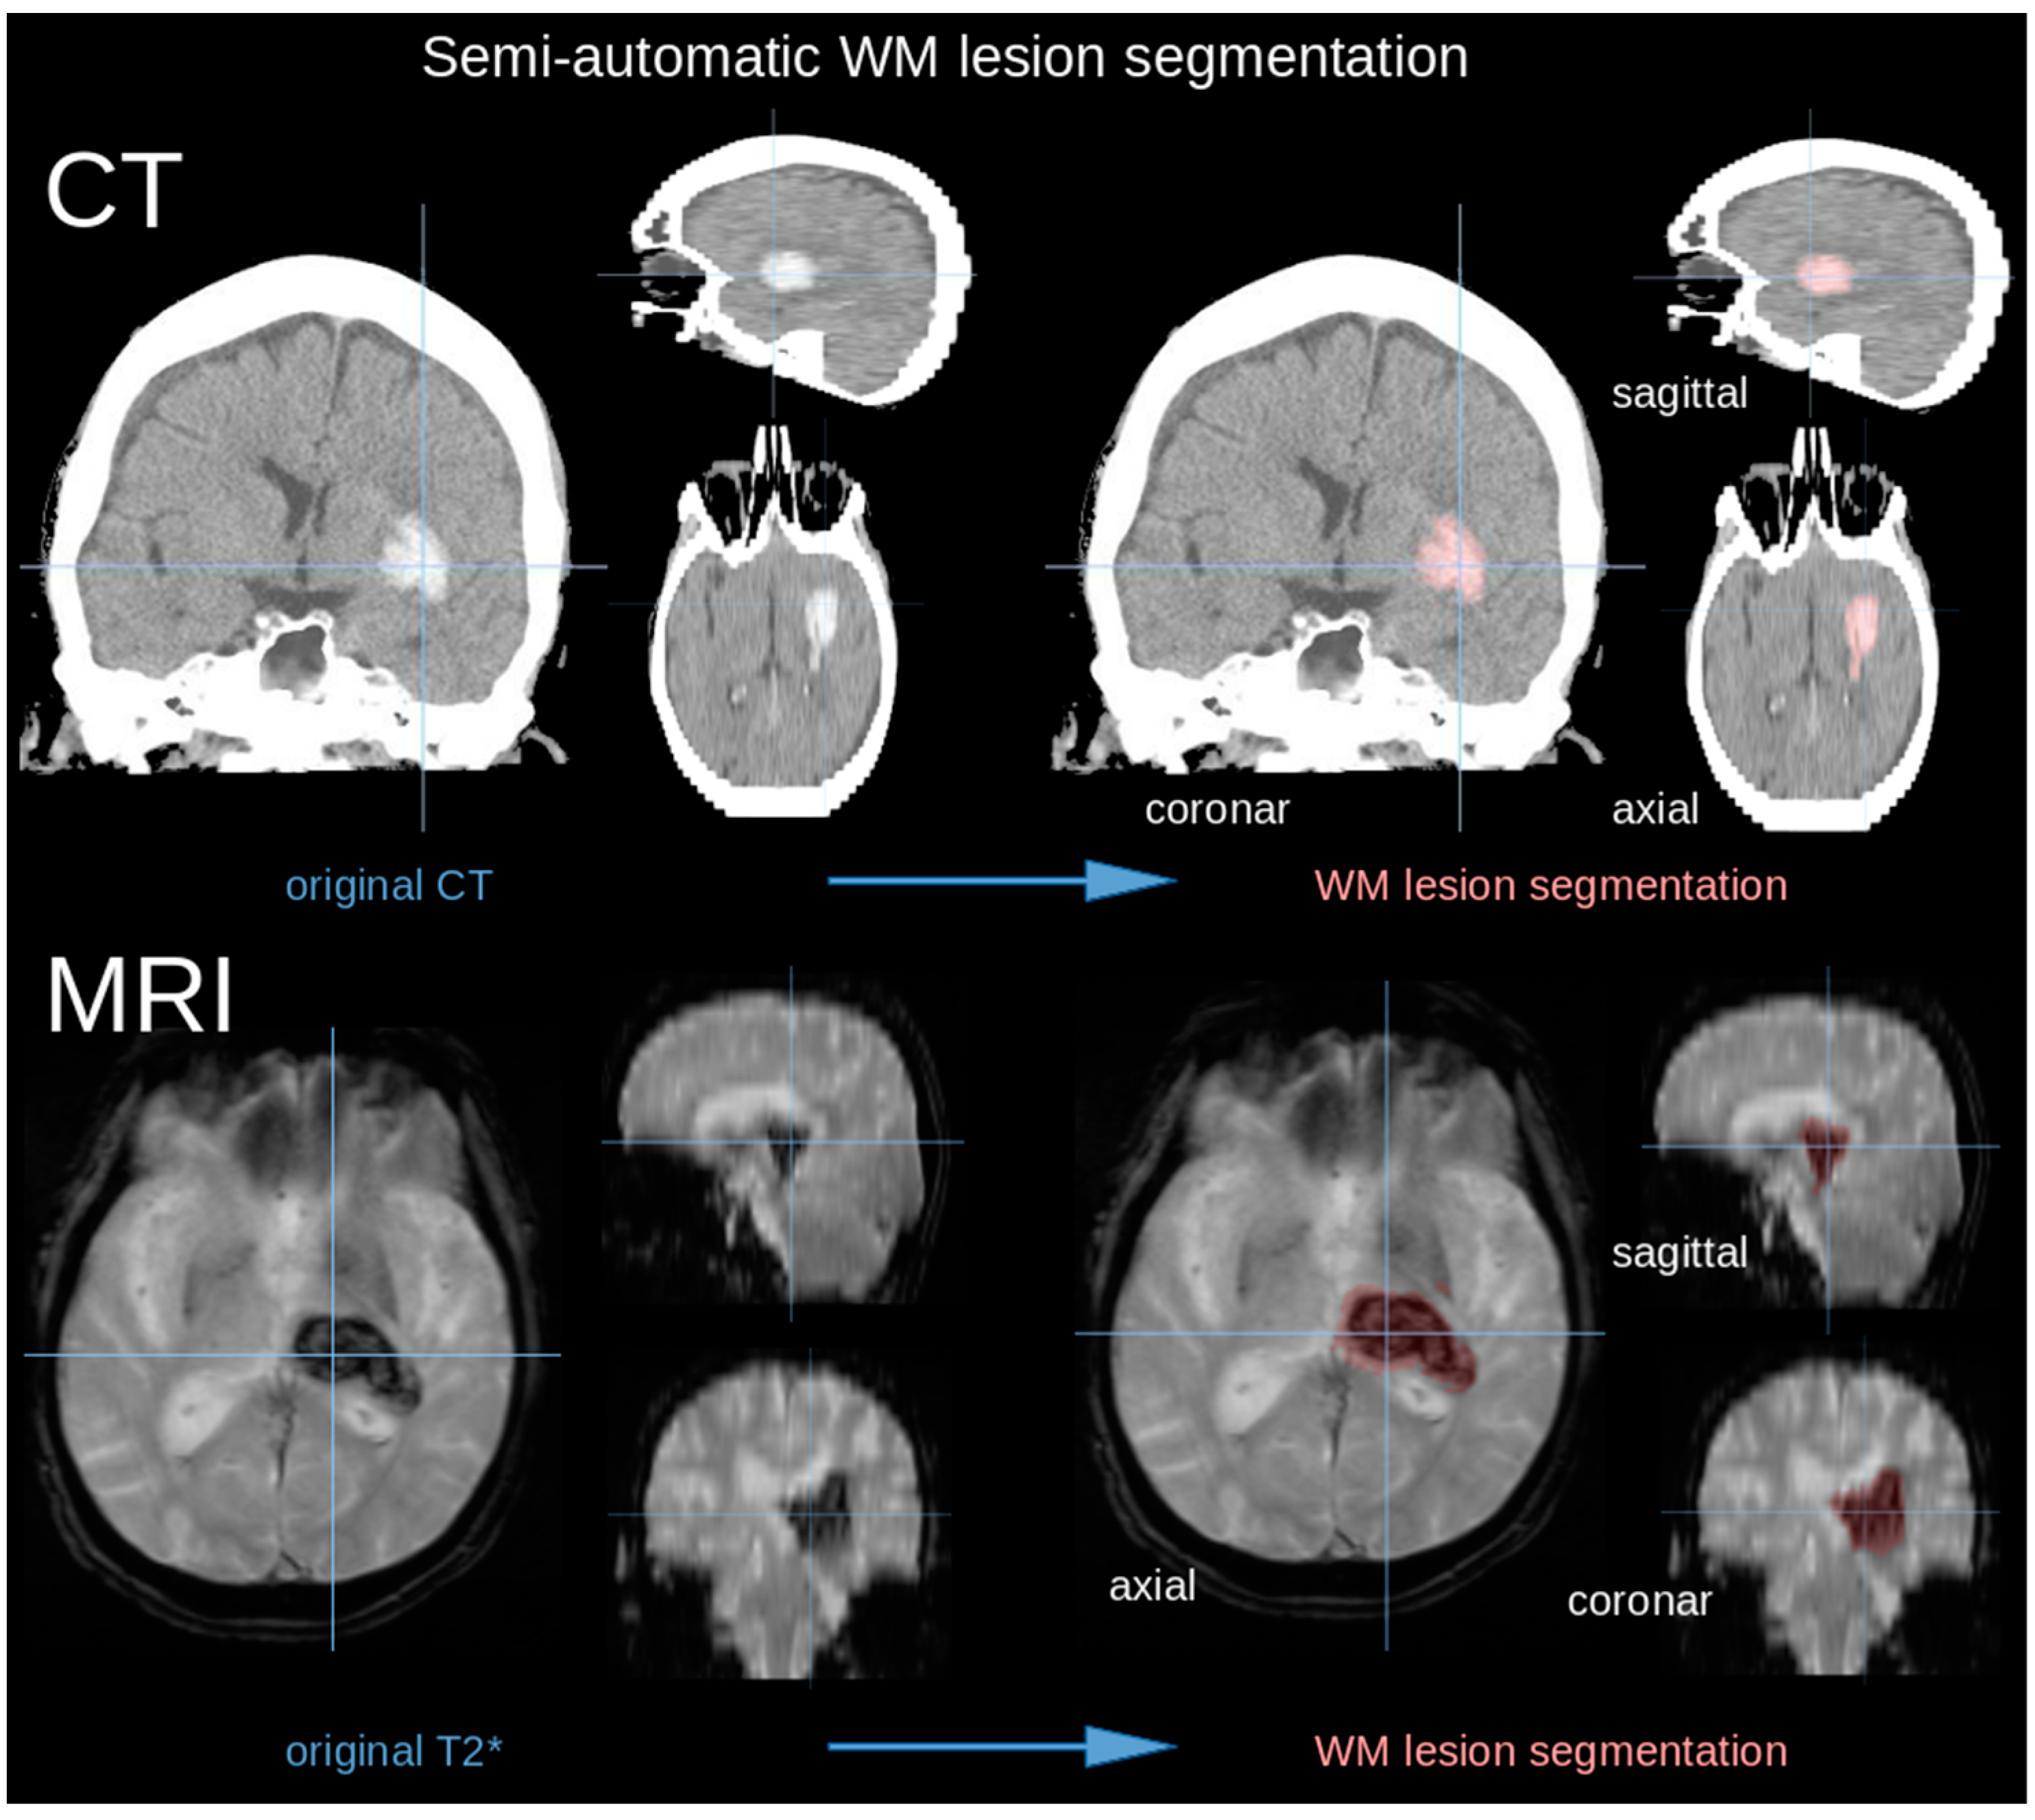

The database consisted of standard clinical magnetic resonance imaging (MRI) protocols acquired on a 1.5 Tesla MRI (Magnetom TIM Symphony, Siemens, Erlangen, Germany) or, in case of contraindication for MRI, computed tomography (CT) (Somatom Emotion 16 eco, Siemens, Erlangen, Germany) [22]. The T2* MRI scans consisted of 40–50 coronar slices (thickness 3.0 mm) with an in-plane resolution of 0.43 × 0.43 mm2; the CT protocol consisted of 40 axial slices (thickness 5.0 mm) with an in-plane resolution of 0.33 × 0.33 mm2. Hematoma volume was measured on MRI or CT scans. The Tensor Imaging and Fiber Tracking (TIFT) software was used for processing of the imaging data [23,24,25]. MRI or CT scans were transformed into a 3-dimensional isotropic grid with a size resolution of 0.5 mm. For the volumetric measurement of ICH, lesion-related voxels were identified by an operator-defined intensity range using semiautomatic delineation of the hyperdense bleeding tissue in CT or hypointensity in T2*-MRI (Figure 1). Patients with surgical hematoma evacuation were excluded from the measurement of the follow-up images due to the lack of comparability.

Figure 1.

(Upper panel) CT scan in coronar, axial, and sagittal slice representation (see crosshairs) with colored infarct area (right). (Lower panel) MRI scan in axial, sagittal, and coronal slice representation (see crosshairs) with segmented infarct area (right).